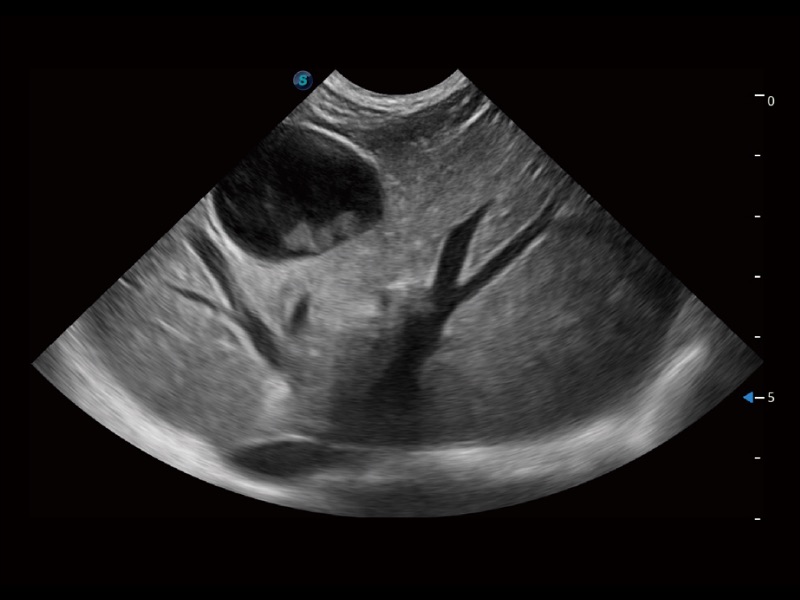

一键自动识别膀胱壁及自动测量膀胱容积,不受膀胱形状和大小的限制,帮助医生快速精准获得测量的数据。

ProPet 70专为动物医生设计,对不同的动物体型和生理结构作出了针对性的优化。通过动物影像专用软件,可满足个性化的应用需求,帮助动物医生获得更精确的诊断数据。